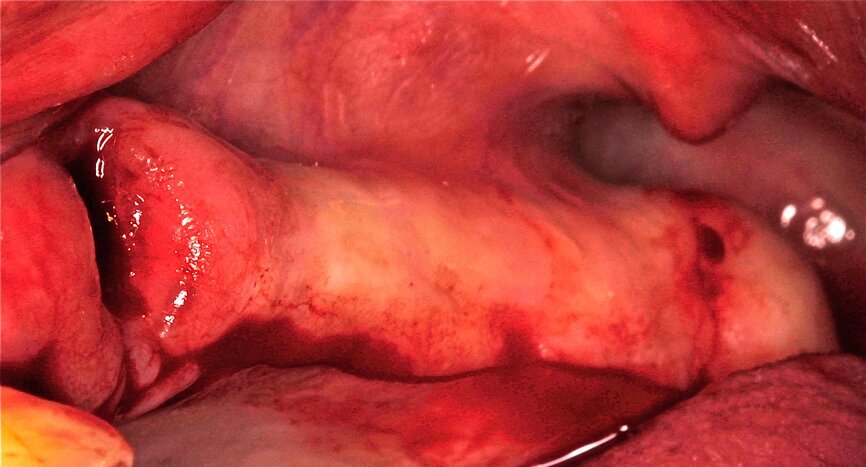

ELEVACION DE SENO ATRAUMATICA28

Fig. 25 Figura 25

1. Anestesia infiltrativa vestibular y lingual para la anestesia del nervio infraorbitario, alveolar posterosuperior y palatino mayor.

2. Incisión paracrestal 2 mm hacia palatino con hoja de bisturí 15C, intrasurcular los dientes adyacentes

Fig. 26 Figura 26

3. Elevación del colgajo mucoperióstico a espesor total exponiendo la cresta ósea.